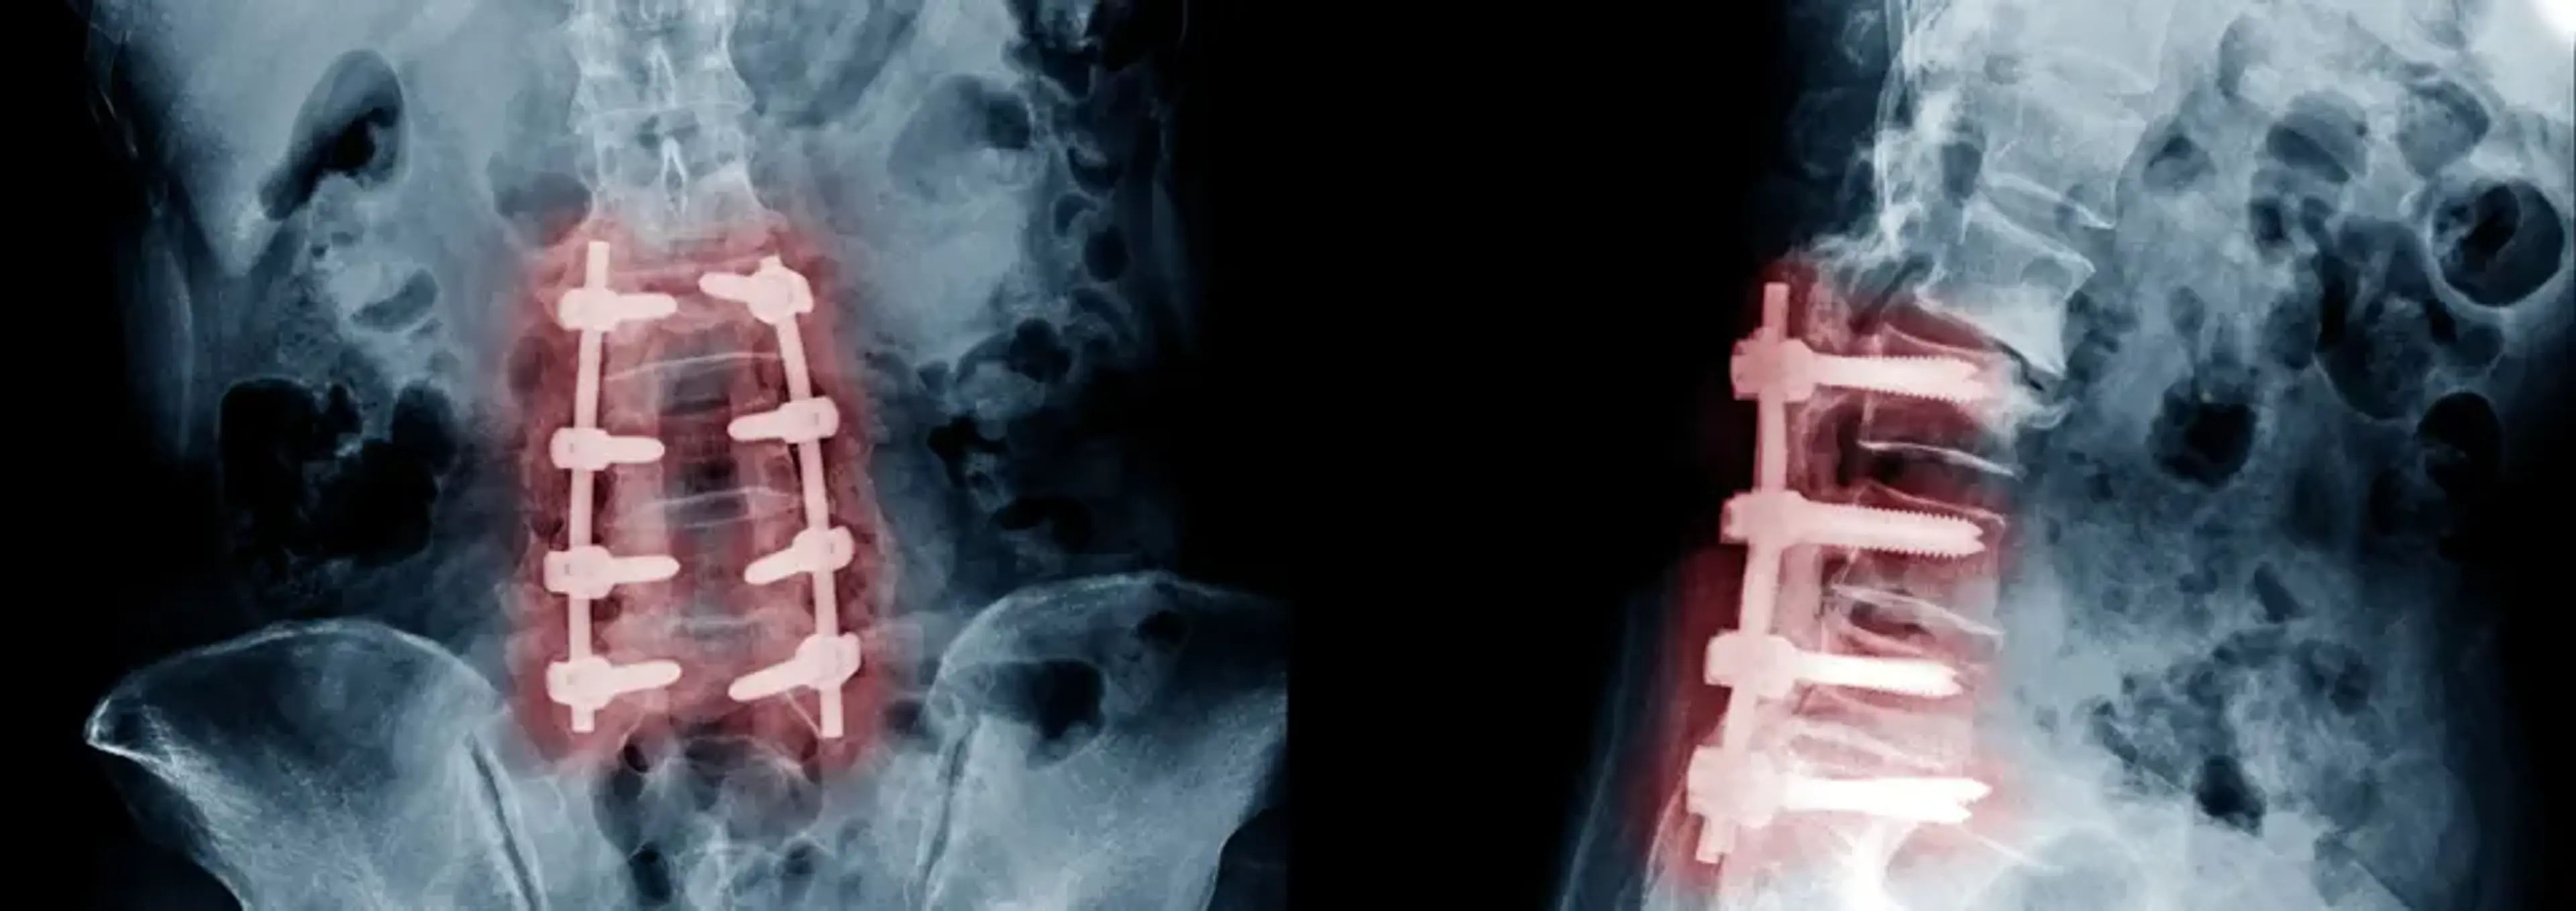

退行性椎间盘病是指椎间盘(脊柱的缓冲垫)随着时间推移逐渐退化破损,导致疼痛、炎症和神经受压。干细胞疗法可以帮助修复椎间盘,减轻疼痛并改善活动能力。

脊柱管狭窄是指脊柱管变窄,通常由椎间盘和韧带等脊柱组织退化引起。这种狭窄会压迫脊髓和神经,导致疼痛、麻木和无力等症状。干细胞可以促进组织再生,有助于缓解神经压力和症状。

椎间盘突出是指椎间盘内部的核心部分穿过外层裂口,可能压迫邻近神经。将干细胞注射到受影响区域可以帮助修复椎间盘,减少炎症,从而缓解疼痛和不适。

小关节骨关节炎是指连接椎骨的小关节软骨退化,导致疼痛和僵硬。将干细胞注射到关节内可以促进软骨再生,减少炎症,从而缓解疼痛并改善功能。